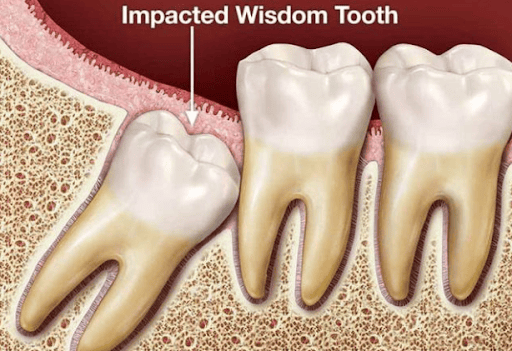

Những kiểu mọc của răng khôn

Răng mọc thẳng thông thường;

Răng mọc lệch khoảng 45 độ;

Răng mọc ngang (lệch 90 độ);

Răng mọc ngược 90 độ

Răng khôn mọc lệch 45 độ chèn vào những răng bên cạnh